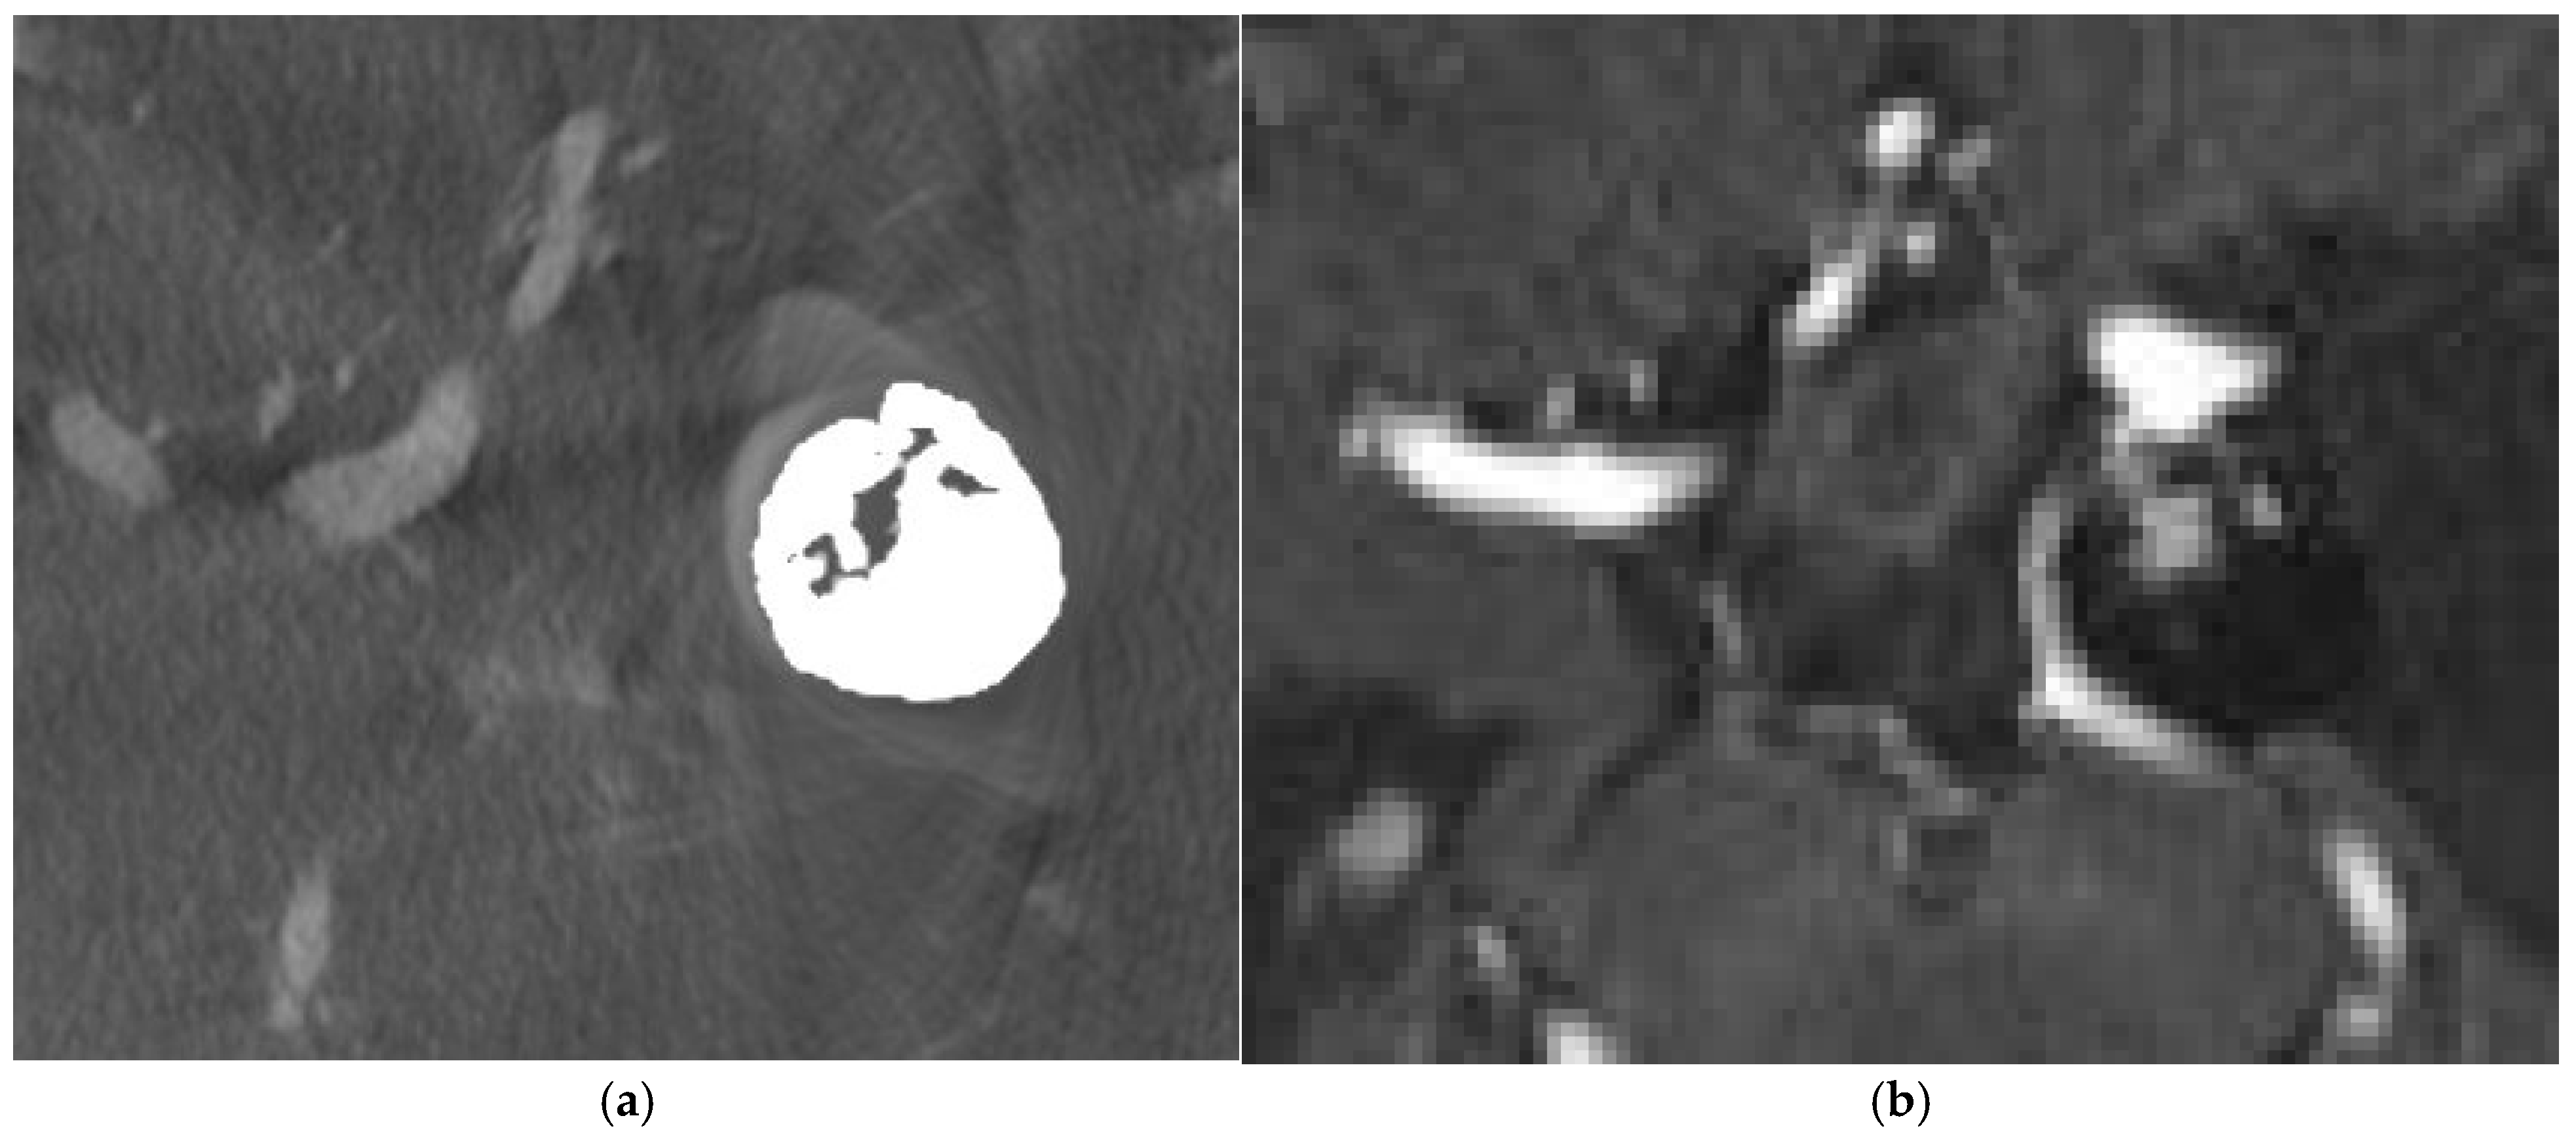

4.1. Case 1

4.2. Case 2

4.3. Case 3